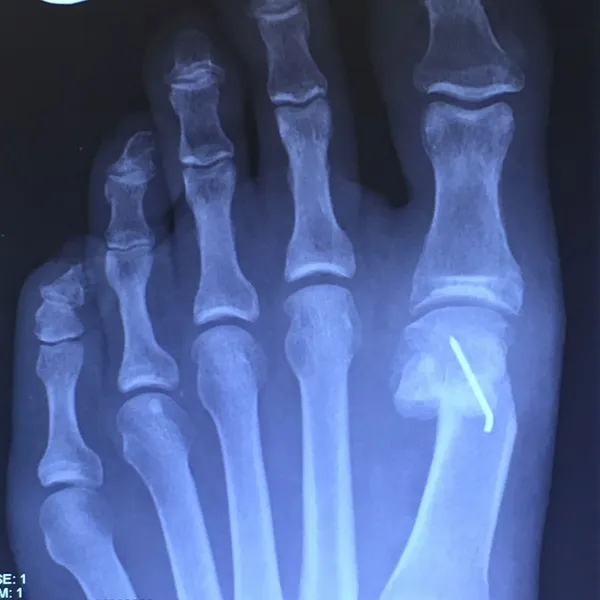

X-rays demonstrating correction of bunion deformity with the great toe deviated laterally (left image) and notice the position of the sesamoid bones which are the small round bones near the joint. The post-surgical film (right image) depicts alignment of the great toe significantly improved and the position of the sesamoid is underneath the 1st metatarsal head where it should be. This is a case where two surgical screws were used to fixate the correction.

Post-surgical repair of the same patient bunion deformity with the great toe now in rectus (straight) position with surgically placed screws in the head of the first metatarsal that were used to secure fixation of the cut made across the bone to translate the head of the bone laterally in order to reduce the deformity. The screws will remain in place even after the bone heals.